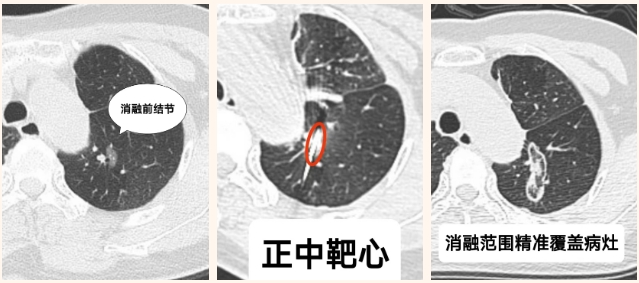

我院多学科团队评估后,决定采用创新的精准导航下肺结节消融方案。在最新一代AI机器人导航系统辅助下,结合CT实时影像引导,35分钟完成靶向消融,患者术后恢复良好,第二天即康复出院。

此次,我院创新将全麻与AI机器人精准导航技术融合。通过 AI机器人导航一次扫描完成坐标配准,误差更小。在麻醉方式上,多数医院采用局麻,我院采用全麻与导航协同,让患者无痛、身体放松,呼吸平稳可控,避免局麻时因疼痛、紧张造成的体位移动,为精准手术创造良好条件,极大提升患者体验和治疗效果。在多学科协作方面,我院多学科团队从评估、手术到康复全程配合,为患者提供更优质服务,推动技术全面发展。